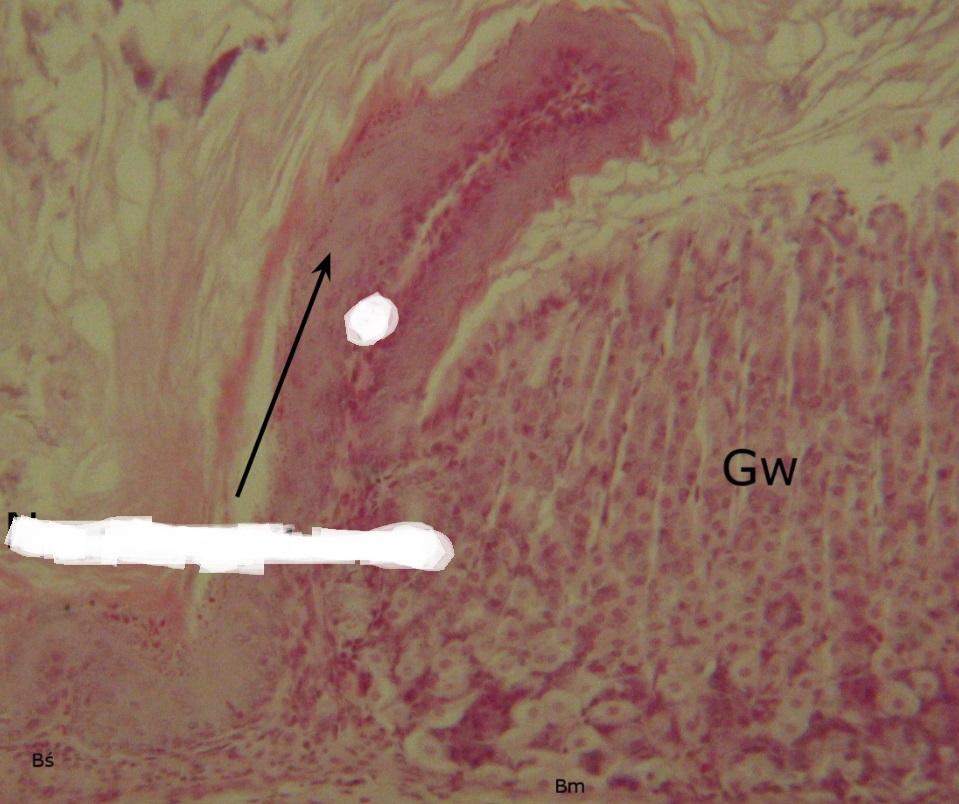

Pytanie 391

strzałka pionowa - dołek żołądkowy, strzałka pozioma - pólko żolądkowe, czyli powierzchnia obejmująca dołek i otaczające go komórki nabłonka (dno i trzon żołądka)